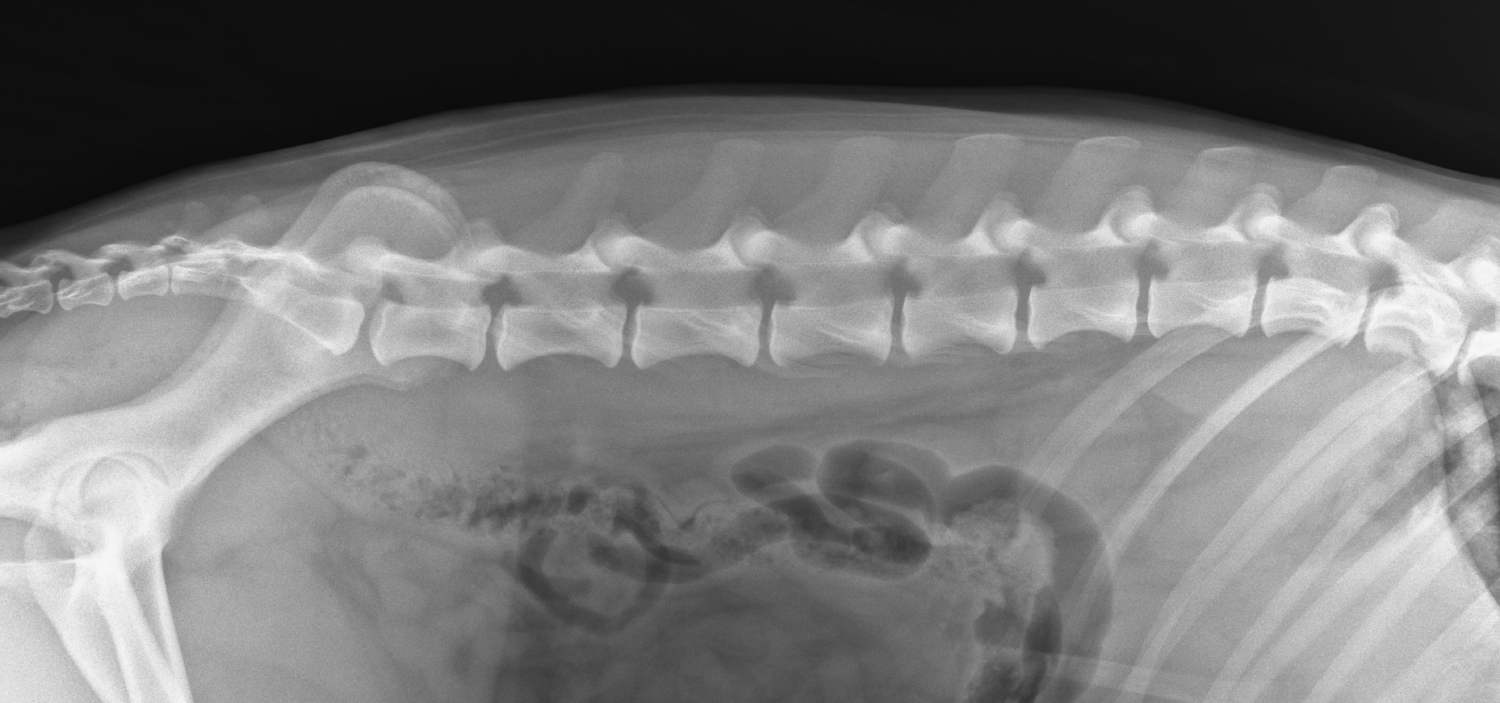

Klinicky pak posuzujeme držení těla, chůzi a celkové chování pacienta. Důraz klademe na citlivé prohmatání postižených oblastí se snahou určit místo bolestivosti a možnou strukturu těla, ze které vychází. Velmi vhodné je provést vyšetření krve, vč. zánětlivých markerů. Nezastupitelnou roli má RTG vyšetření. V indikovaných případech pak CT, popř. magnetická rezonance.

2. RTG snímek bederní páteře psa.